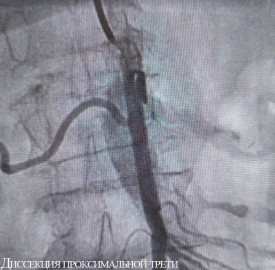

Обеим женщинам было выполнено эндоваскулярное вмешательство — без разрезов, через прокол в бедренную артерию в паху был введен зонд, с помощью которого врачи удалили тромбы из просветов сосудов. Обе пациентки были в сознании во время операции, и прямо на операционном столе у них прошел болевой синдром.

Оперировал обеих больных эндоваскулярный хирург Нарек Вачаганович Марукян. Первая пациентка была выписана на третий день после лечения. Перед этим ей выполнили коронарографию (поскольку поступила она с подозрением на инфаркт), при этом вмешательство на сосудах сердца не потребовалось. Вторую больную выписали на амбулаторное лечение через неделю после операции.